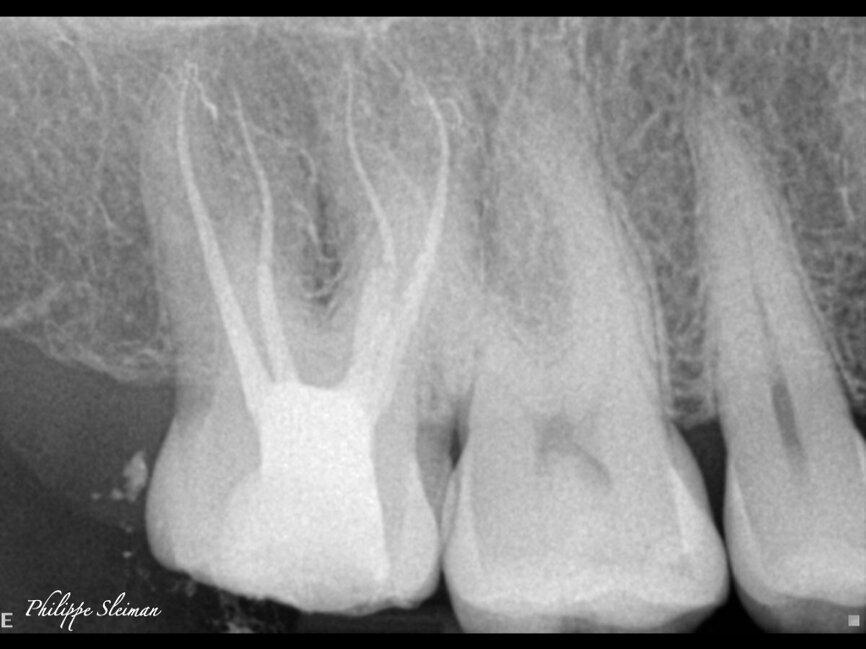

The preoperative radiograph and access cavity under the operating microscope (Images: Philippe Sleiman)

Case 1

The preoperative radiograph (Fig. 1) revealed that the roots had an uncommon shape, particularly regarding the palatal root, the periodontal ligament and the apex of the mesial root. Upon creating the access cavity (Fig. 2), under the operating microscope, I noticed bleeding from the mesiopalatal angle. Extending the access cavity to that side led to the discovery of a separate canal, which may have been a second palatal or an independent mesial canal.

For shaping, you need to start, after establishing a glide path, with 21 mm stainless-steel hand files. I use a 17 mm orifice opener because it allows me to work way in the back with indirect vision, and this step will shape the first part of the canal, making it easy for the remaining rotary files to follow the path that has been created. The final radiographs revealed four separate root canals (Fig. 3). Figure 4, a micro-CT scan done by Dr Volokitin, shows almost the same anatomy.